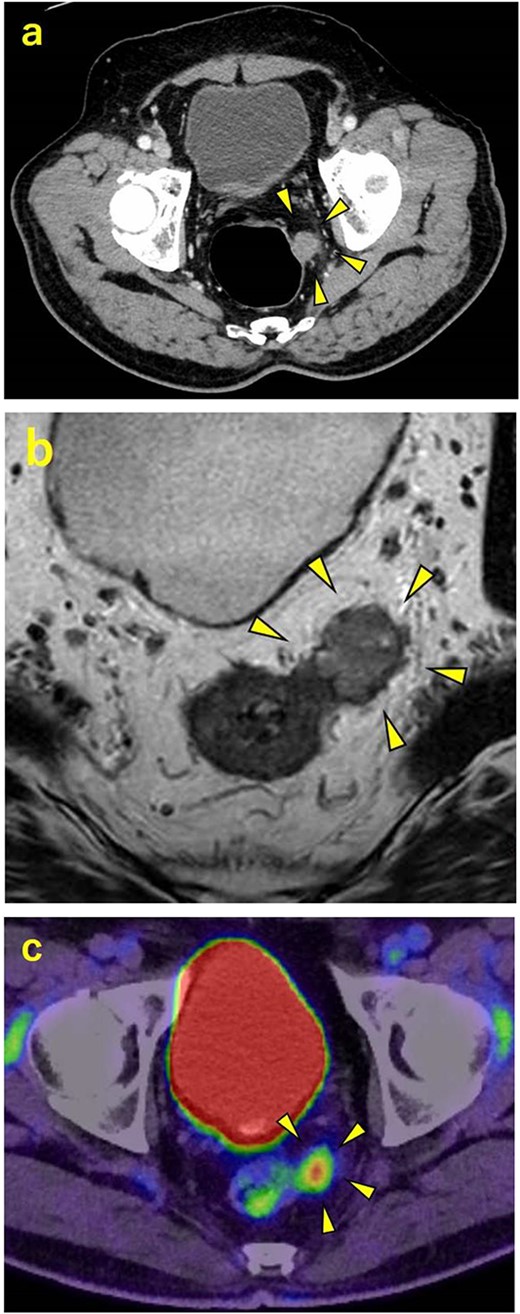

A 70-year-old man was referred to our urology department for prostate cancer based on a mass contiguous with the rectum seen on an imaging scan. He had a Gleason score of 4 + 5, seminal vesicle invasion, and pelvic lymph node metastasis. A month of combined androgen blockade therapy had reduced his prostate-specific antigen (PSA) levels from 25.29 to 10.81 ng/ml. He was diagnosed with rectal cancer at 68 years old and had undergone an endoscopic mucosal resection (EMR) and curative resection. The tumor marker levels were as follows: carcinoembryonic antigen, 2.8 ng/ml and carbohydrate antigen 19–9, 25.4 U/ml. Lower gastrointestinal endoscopy revealed only an EMR scar in the rectum. Computed tomography (CT) revealed a 20-mm large extramural growth-type mass on the left wall of the rectum, 9 cm from the anal verge (Fig. 1a). The mass had a weak enhancing effect and somewhat irregular limbus, and was continuous with the rectus muscularis. The mass was close to the ureter-hypogastric fascia and was suspected to have invaded the pelvic plexus. We observed an enhancing effect in the left lobe of the prostate, and an enlarged left lateral lymph node. No distant metastases were found in other organs, including the bones. Magnetic resonance imaging (MRI) revealed that the mass may have originated from the muscularis propria of the rectum (Fig. 1b). The prostate carcinoma partially touched the rectum beyond the capsule, with no evidence of invasion. 18F-fluorodeoxyglucose-positron emission tomography-CT (FDG PET-CT) showed accumulation in the mass, with a maximum standardized uptake value of 5.96. There was no accumulation in any other organ, including the prostate and pelvic lymph nodes (Fig. 1c). After examination, gastrointestinal stromal tumor (GIST), neuroendocrine tumor (NET), and lymph node metastatic recurrence of rectal cancer were considered as differential diagnoses. Endoscopic ultrasound-guided fine needle aspiration (EUS-FNA) was scheduled for pathological diagnosis. However, since the patient denied the EUS-FNA and preferred an early resection, we performed only surgery. During the laparoscopic low anterior resection, a laparoscopic ultrasonography probe was applied to the mesorectum to identify the mass (Fig. 2a). A hypoechoic area was observed in the left mesorectum (Fig. 2b). Since we suspected invasion into the ureter-hypogastric fascia, the area around the lesion was resected, with partial merging of the pelvic plexus. Postoperatively, the patient had a mildly relieved neurogenic bladder and was discharged on postoperative Day 8. The resected specimen showed a well-defined 18 × 16 mm large borderline mass predominantly on the lower rectal adventitia (Fig. 3a). The lesion was non-contiguous and located contralateral to the EMR scar. Histopathological findings revealed that the mass was poorly differentiated carcinoma and grew to compress the muscularis propria (Fig. 3b). The tumor was immunohistochemically positive for CK AE1/AE3 and NKX3.1 (Fig. 4a); partially positive for PSA (Fig. 4b); and negative for CK7, CK20, CDX2 (Fig. 4c), TTF1, chromogranin A, synaptophysin, CD56, C-KIT, and SOX10. Therefore, the tumor was diagnosed with rectal metastasis of prostate cancer. Cancer metastases of similar histology were also found in other resected lymph nodes. Enzalutamide was started 2 months postoperatively, but due to tumor and metastatic lymph node enlargement, docetaxel treatment was started at 5 months postoperatively. However, the disease continued to progress, and he died 10 months after surgery.

Contrast-enhanced CT, contrast-enhanced MRI, and PET. (a) CT showing a 20-mm large extramural growth-type mass on the left wall of the rectum, 9 cm from the anal verge. (b) MRI showing that the mass may have originated from the muscularis propria of the rectum. (c) PET showing an accumulation in the mass with a maximum standardized uptake value of 5.96.